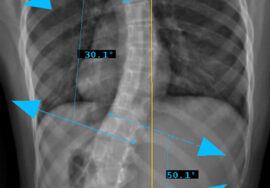

دراسة جديدة شملت 79 مريضًا مصابين بالاعوجاج قسمت المرضى إلى عدة أنواع:

اعوجاج صدري منفرد.

اعوجاج صدري قطني (Thoracolumbar).

اعوجاج قطني (Lumbar).

اعوجاج مزدوج صدري.

اعوجاج مزدوج رئيسي (Double Major).

تم قياس نشاط العضلات باستخدام جهاز تخطيط العضلات الكهربائي (EMG). أجري الاختبار أثناء أداء تمرين “السوبرمان”، وهو رفع الذراعين والساقين مع الاستلقاء على البطن.